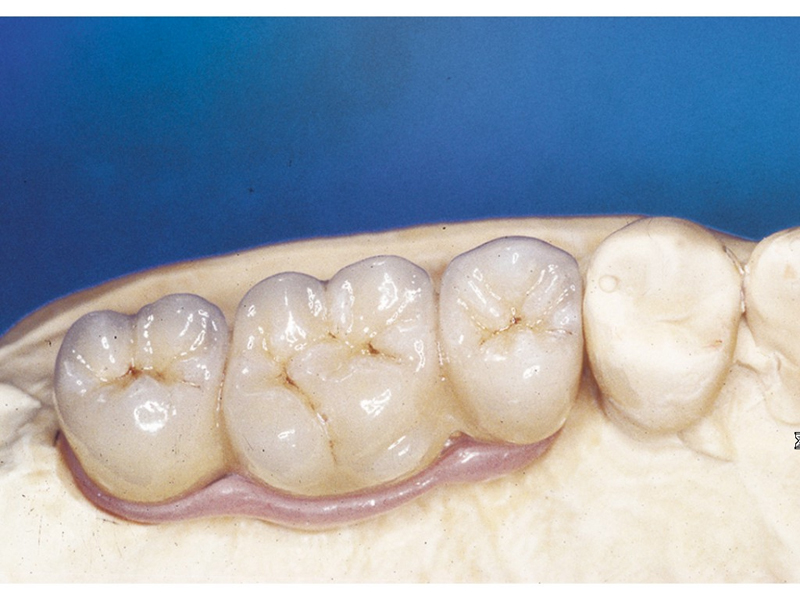

Protetické řešení může být pomocí můstku, který je kotvený na implantátech nebo pomocí jednotlivých korunek na implantátech.

V zásadě je možné do těchto můstků zařadit i přirozené zuby, zejména pokud je potřeba tyto zuby ošetřit proteticky - korunkami. Korunky nebo můstky mohou být na implantáty nacementovány nebo přišroubovány.

V případě chybění většího počtu zubů v postranních úsecích čelistí je možné ošetření pomocí implantátů, které nahradí ošetření pomocí snímacích náhrad kotvených na zbývajících zubech nebo patře.

Podmínkou je opět dostatečné množství kosti.